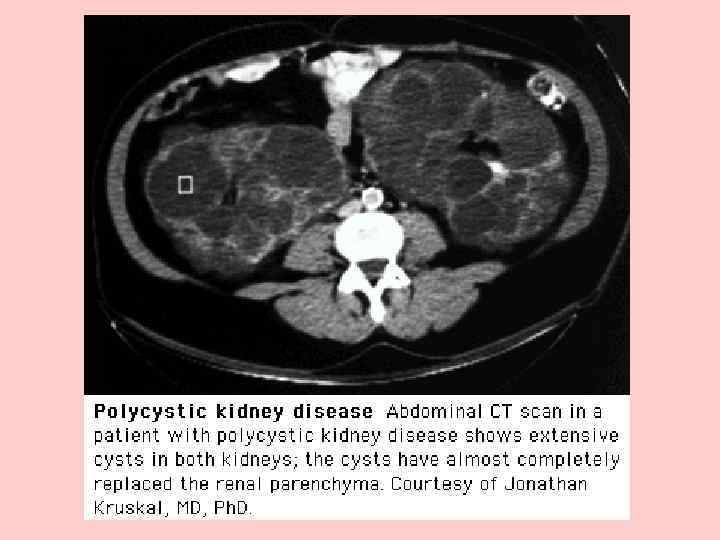

В основе инструментальной диагностики этого заболевания лежит выявление кист — основного клинического маркера поликистоза почек. С этой целью в настоящее время широко используют современные методы диагностики почечных кист — ультразвуковое исследование, сцинтиграфию и компьютерную томографию. При ультразвуковом исследовании и сцинтиграфии выявляются кисты размером более 1, 5 см, при компьютерной томографии — более мелкие (от 0, 5 мм).

Для лиц с отягощенной наследственностью критерием диагноза является один из приведенных ниже вариантов соотношения количества кист в почках и возраста, даже при отсутствии клинических признаков болезни [Ravine D. et al. , 1994]: • наличие 2 кист в одной или обеих почках в возрасте до 30 лет; • наличие по 2 кисты в каждой почке в возрасте 30— 59 лет; • наличие не менее 4 кист в каждой почке в возрасте старше 60 лет.

Кисты в почках и печени являются определяющим фактором для всей группы кистозных болезней. Кисты представляют собой наполненные жидкостью структуры различной величины, выстланные одним слоем измененного канальцевого эпителия. Кисты обнаруживают: в корковом и мозговом слое почек, в области лоханок почек и окололоханочной области, реже на полюсах почки. Размер кист и количество жидкости в них широко варьируют: малые кисты (менее 2 мм в диаметре) содержат, как правило, не более 3 мл жидкости, в то время как в больших кистах количество жидкости может исчисляться литрами.

По мере прогрессирования болезни число кист возрастает, увеличиваются их размер и соответственно размер почек, поверхность которых становится неровной, похожей на “виноградную кисть”. Почки при поликистозе могут достигать в длину 40 см и весить более 8 кг [Пытель Ю. А. , 1995].